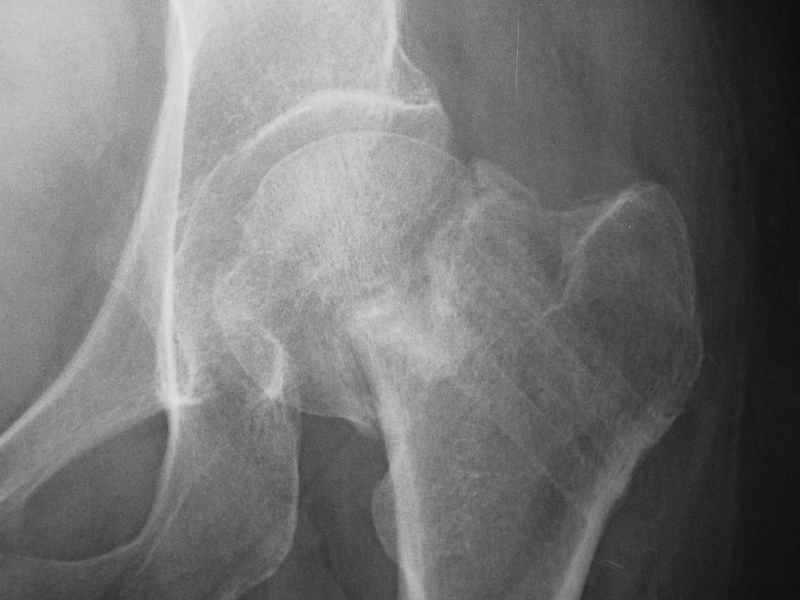

dhs will not correct improper biomechanical environment and may further compromise vascular

integrity consider establish vascular status via mri

and if viable follow with proximal valgus osteotomy

case provided s/p failed fixation